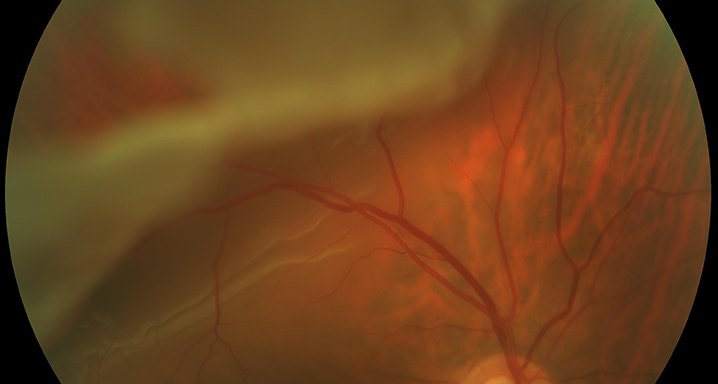

Desprendimiento de retina 22/03/2013

Conceptualmente, por desprendimiento de retina se entiende la separación entre las capas de retina neurosensorial y el epitelio pigmentario de la retina.

- Regmatógenos: es el tipo más común de desprendimiento de retina y lo provoca una rotura de la retina que puede aparecer después del desprendimiento del vítreo.

Es indispensable un examen oftalmológico minucioso que incluya un examen completo de la retina periférica para diagnosticar todas las roturas retinianas responsables del desprendimiento. A veces, la tomografía de coherencia óptica y la ecografía ocular son de ayuda para realizar el diagnóstico.

El tratamiento es casi siempre quirúrgico y consiste en reaplicar la retina. El objetivo es adaptar la retina y crear una adhesión entre la retina neurosensorial y el epitelio pigmentario para sellar las roturas retinianas mediante fotocoagulación con láser.